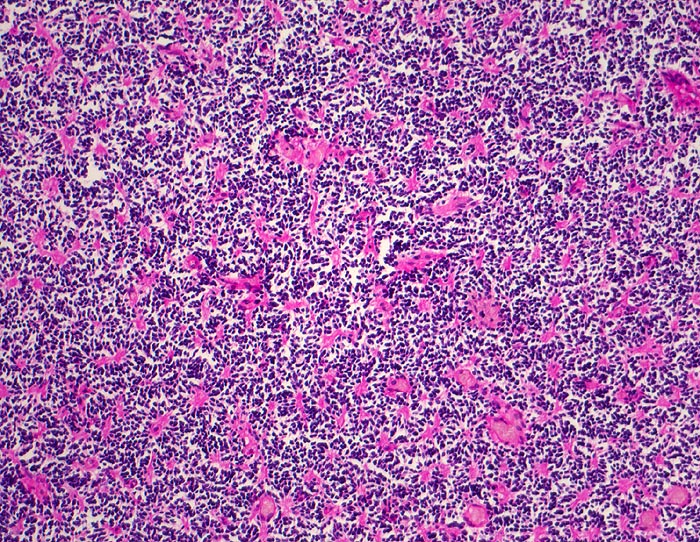

Medulloblastom: Homer Wright Rosetten

Monomorpher Zellrasen mit hyperchromatischen Zellen ohne erkennbares Zytoplasma. Multiple Homer Wright Rosetten erkennbar am eosinophilen Zentrum aus Zellfortsätzen.

Knabe mit Kopfschmerzen und morgendlichem Erbrechen ohne Übelkeit